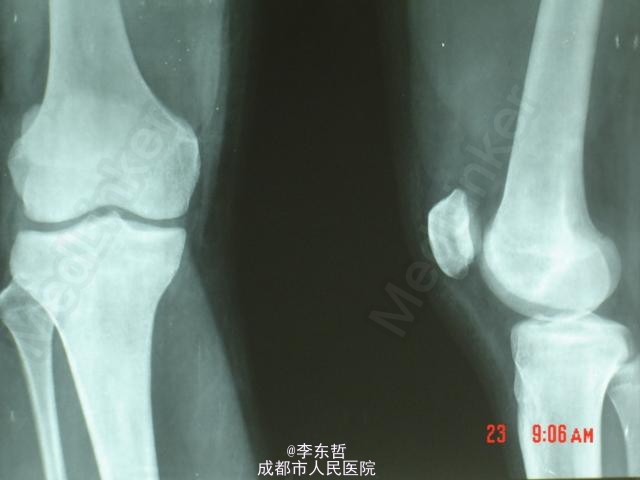

髌骨矢状位骨折

患者男,17岁,车祸致伤右膝,肿胀疼痛,能下地行走,考虑但病人年龄小,骨折愈合快,给予患肢功能位固定6周。